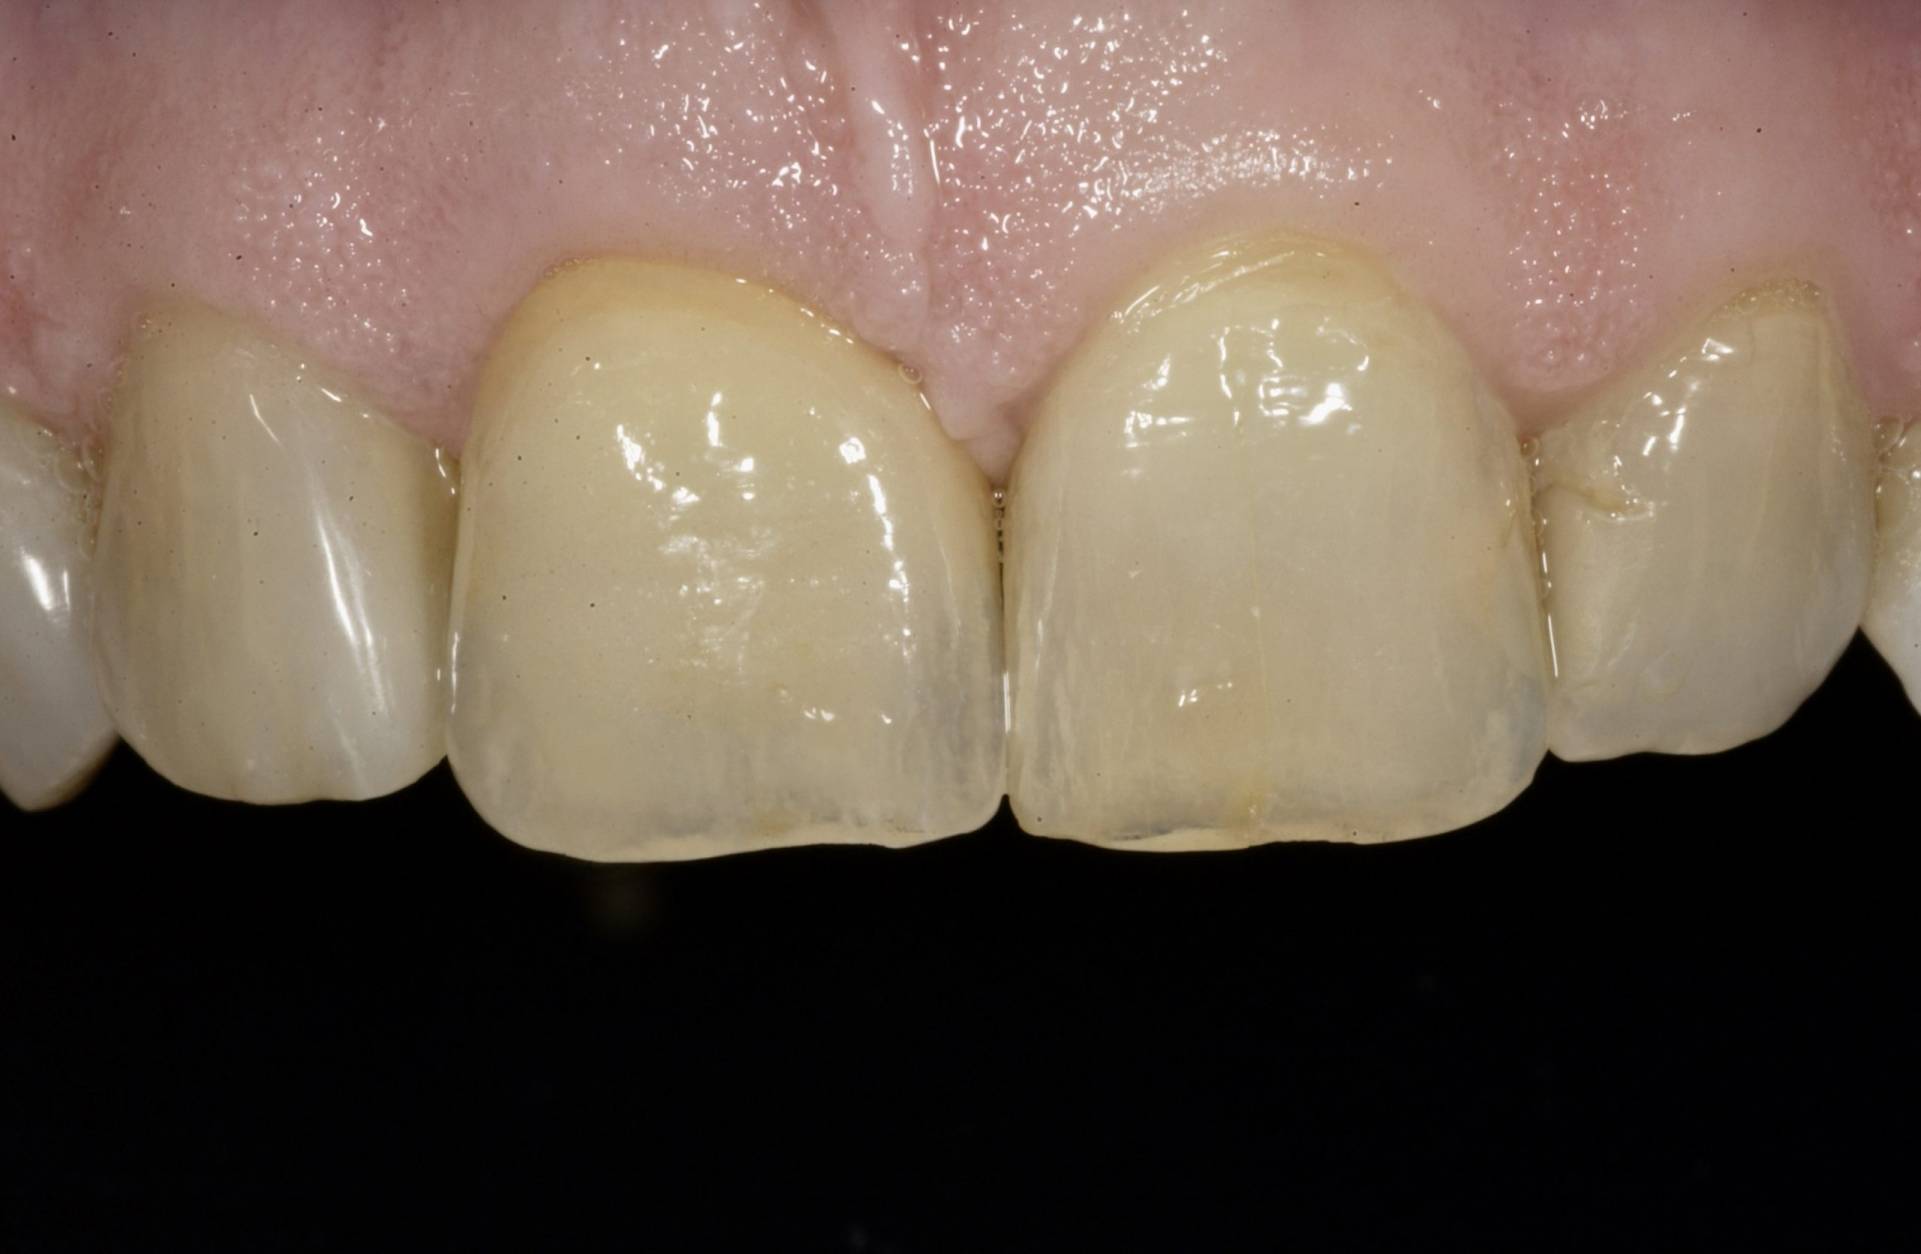

Das Ziel ist eine funktionell und ästhetisch perfekte Versorgung, die sich harmonisch in das bestehende Gebiss einfügt – für langfristige Stabilität, Sicherheit und ein natürliches Gefühl beim Kauen und Sprechen.